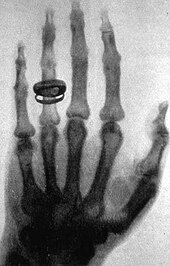

Am 28. Dezember 1895 veröffentlichte Wilhelm Conrad Röntgen seine Studie Über eine neue Art von Strahlen; einen Monat später berichtete er in einer Vorlesung erstmals über die geheimnisvollen „X-Strahlen“ und röntgte vor den Augen der Zuschauer eine Hand des Schweizer Anatomie-Professors Rudolf Albert von Kölliker. Die belichtete Aufnahme – das Bild ist bis heute bekannt – zeigt deutlich erkennbar die Handknochen. Diese Erfindung löste große Begeisterung aus und revolutionierte die Medizin schnell. Die New York Sun sprach von einem „Triumph der Wissenschaft“: Röntgen habe „ein Licht entdeckt, das Holz und Fleisch durchdringt“.[10]